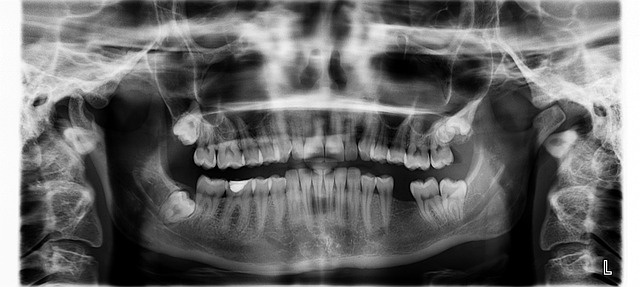

사랑니 발치의 경우, 의사 선생님께서 미리 사랑니의 뿌리가 나있는 모양 등을 봐야 하기 때문에 엑스레이 촬영이 필수입니다. 엑스레이를 찍기 전에 착용하고 온 귀걸이와 목걸이를 빼고 대기해달라고 하시는데요, 비싼 귀금속을 치과에서 허둥지둥 빼고 보관하다가 자칫하면 잃어버릴 수도 있으니 집에서 미리 빼고 가시는 것을 추천드립니다.

- 치과에 도착하면 가장 먼저 고혈압이나 당뇨 등 기저질환이 있는지 물어보고 엑스레이를 찍습니다.

- 엑스레이 결과가 나오면 의자에 앉아 사진을 같이 보면서 현재 상태와 발치 과정에 대한 설명을 듣습니다.